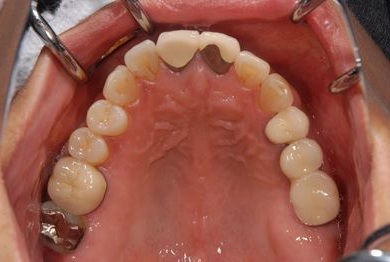

骨再生インプラント治療+セラミック治療+歯肉歯槽骨整形手術

| 治療内容 | インプラント2本(ソケットリフト、GBR)、メタルボンドセラミッククラウン3本、歯肉歯槽骨整形手術 | ||||||||||||||||||||||||||||||||